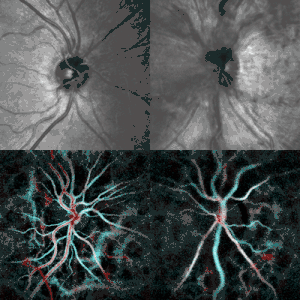

a) Left eye b) and right eye grade IV papilledema, severe elevation and hemorrhages